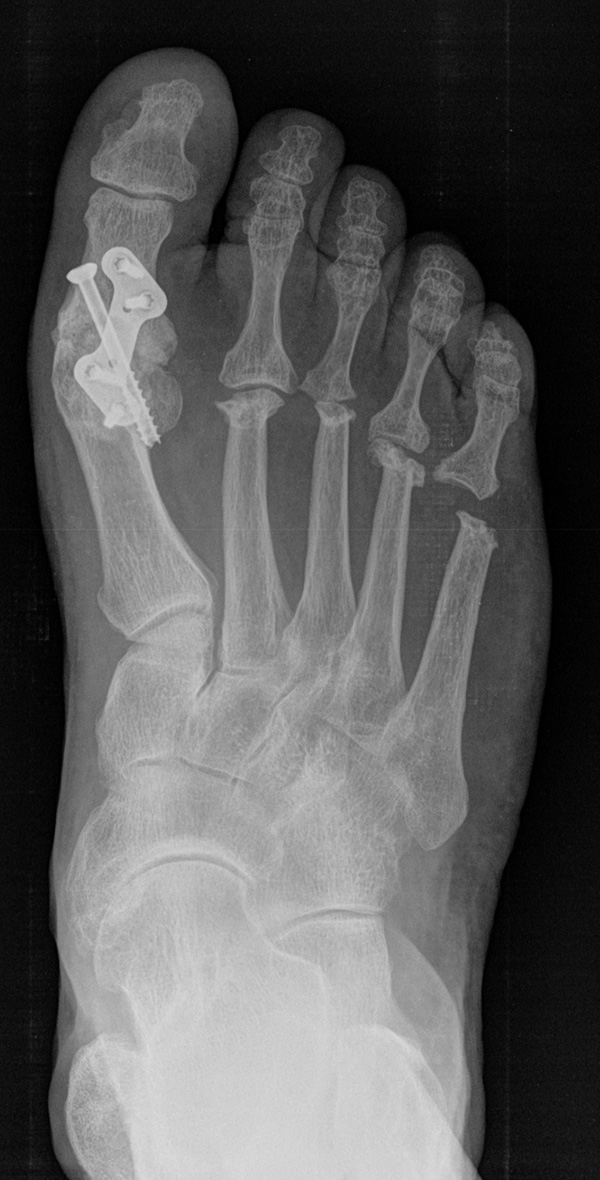

Deutlich bessere Ergebnisse wurden erreicht durch eine Kombination der OP nach Tillmann mit einer Arthrodese des Großzehengrundgelenks oder auch einer Lapidus-Arthrodese 611. Dies wurde bereits 1956 durch Vainio empfohlen, hat sich aber erst in diesem Jahrtausend flächendeckend durchgesetzt 121314.